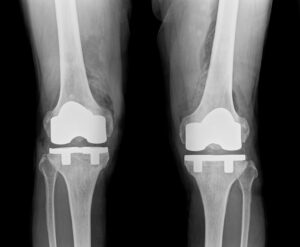

術前

術後

70代女性の変形性足関節症に対し、東京女子医科大学整形外科 炎症性関節疾患外科部門教授の

猪狩勝則先生を招いて人工足関節全置換術を行いました。

特殊なフレームで下腿から踵まで完全に固定して、レントゲン透視画像を確認しながら、

正確に設置していきます。

手術時間は2〜3時間。入院は1ヶ月程度となります。